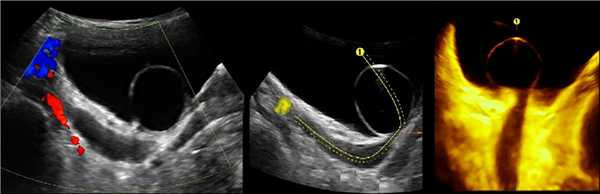

Рисунок. У новорожденного на УЗИ почек определяется гидронефроз (1) и расширенный мочеточник (2) справа. В мочевом пузыре двустороннее уретероцеле (3). При исследовании левой почки структурных изменений не выявлено.

Рисунок. На УЗИ определяется удвоенная чашечно-лоханочная система, расширена лоханка верхнего сегмента (1) и мочеточник на всем протяжение (2, 3), в мочевом пузыре уретроцеле (4). Полное или неполное удвоение чашечно-лоханочной системы возможно увидеть с помощью КТ-урографии.

Рисунок. Двустороннее уретероцеле на УЗИ: в режиме ЦДК из верхушек уретероцеле определяется выброс мочи.